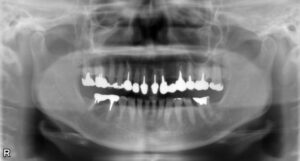

下顎臼歯2本欠損症例

BEFORE AFTER 80歳女性/下2本欠損/インプラント埋込手術 【治療内容】 左下第一小臼歯・第一大…